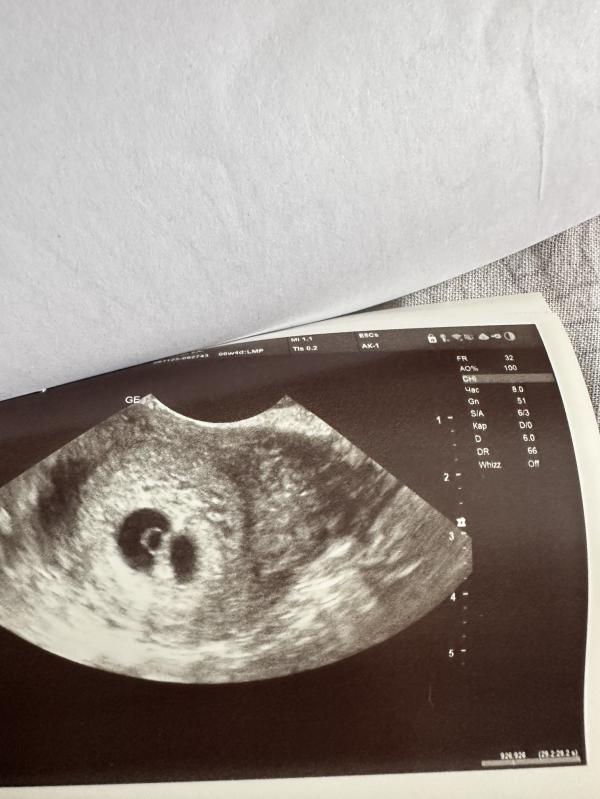

Девочки, привет! Была на Узи, подтвердили беременность малого срока - 5-6 недель.

Но вот меня удивили. Сказали, что визуализируется 2 плодных яйца.

В одном плодном яйце всё увидели: и желточный мешочек, и эмбриончик, и сердцебиение, а во втором плодном яйце ни чего не увидели.

Желтое тело одно. Врач сказал, чере 2 недели нужно посмотреть динамику второго яйца и если подтвердится двойня, то это близнецы.